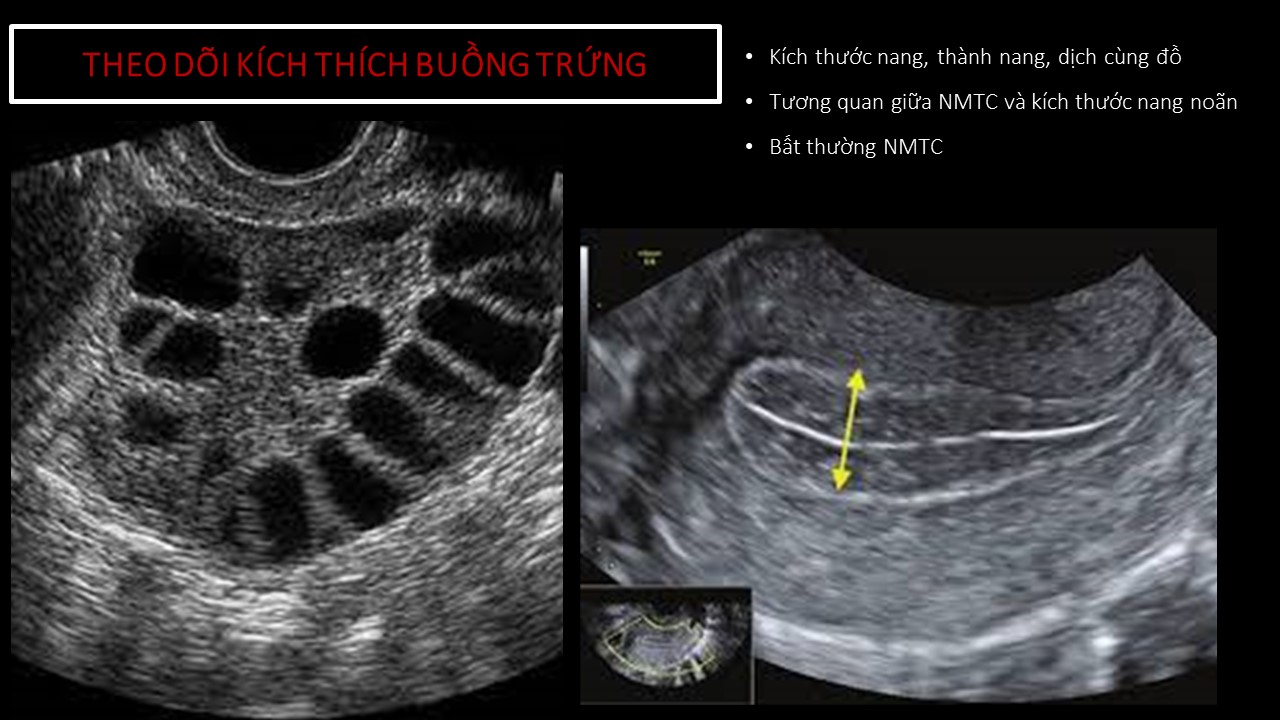

Vai trò của siêu âm trong chẩn đoán và điều trị hiếm muộn